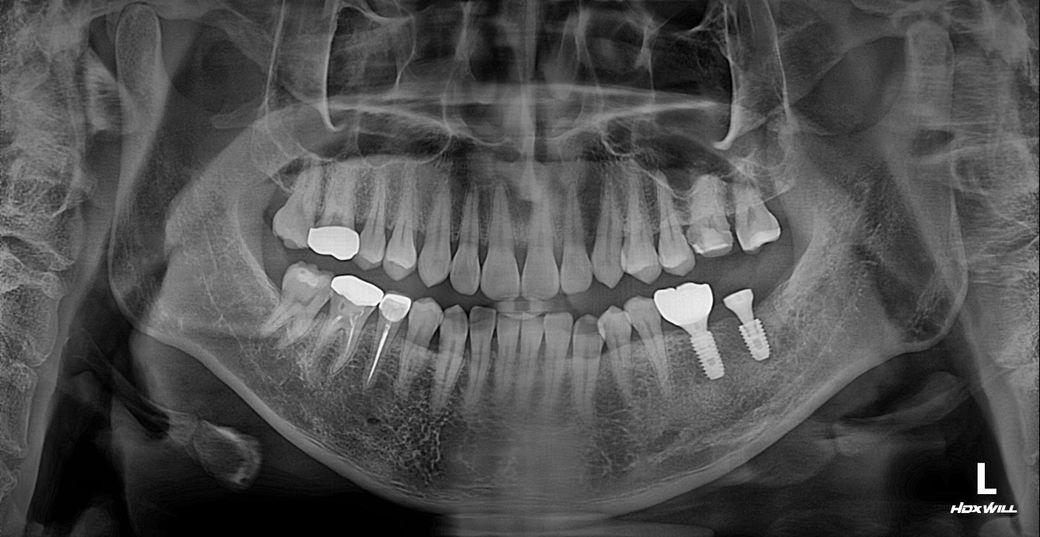

왼쪽 아래 끝에 어금니 자리입니다. X-ray사진으로 지대주까지 설치된 곳입니다.

• 2번 째 사진

파노라마 엑스레이상으론 나사는 잘 심겨진 것 같습니다 임플란트 주위염으로 보이진 않고, 그런 증상도 아닙니다